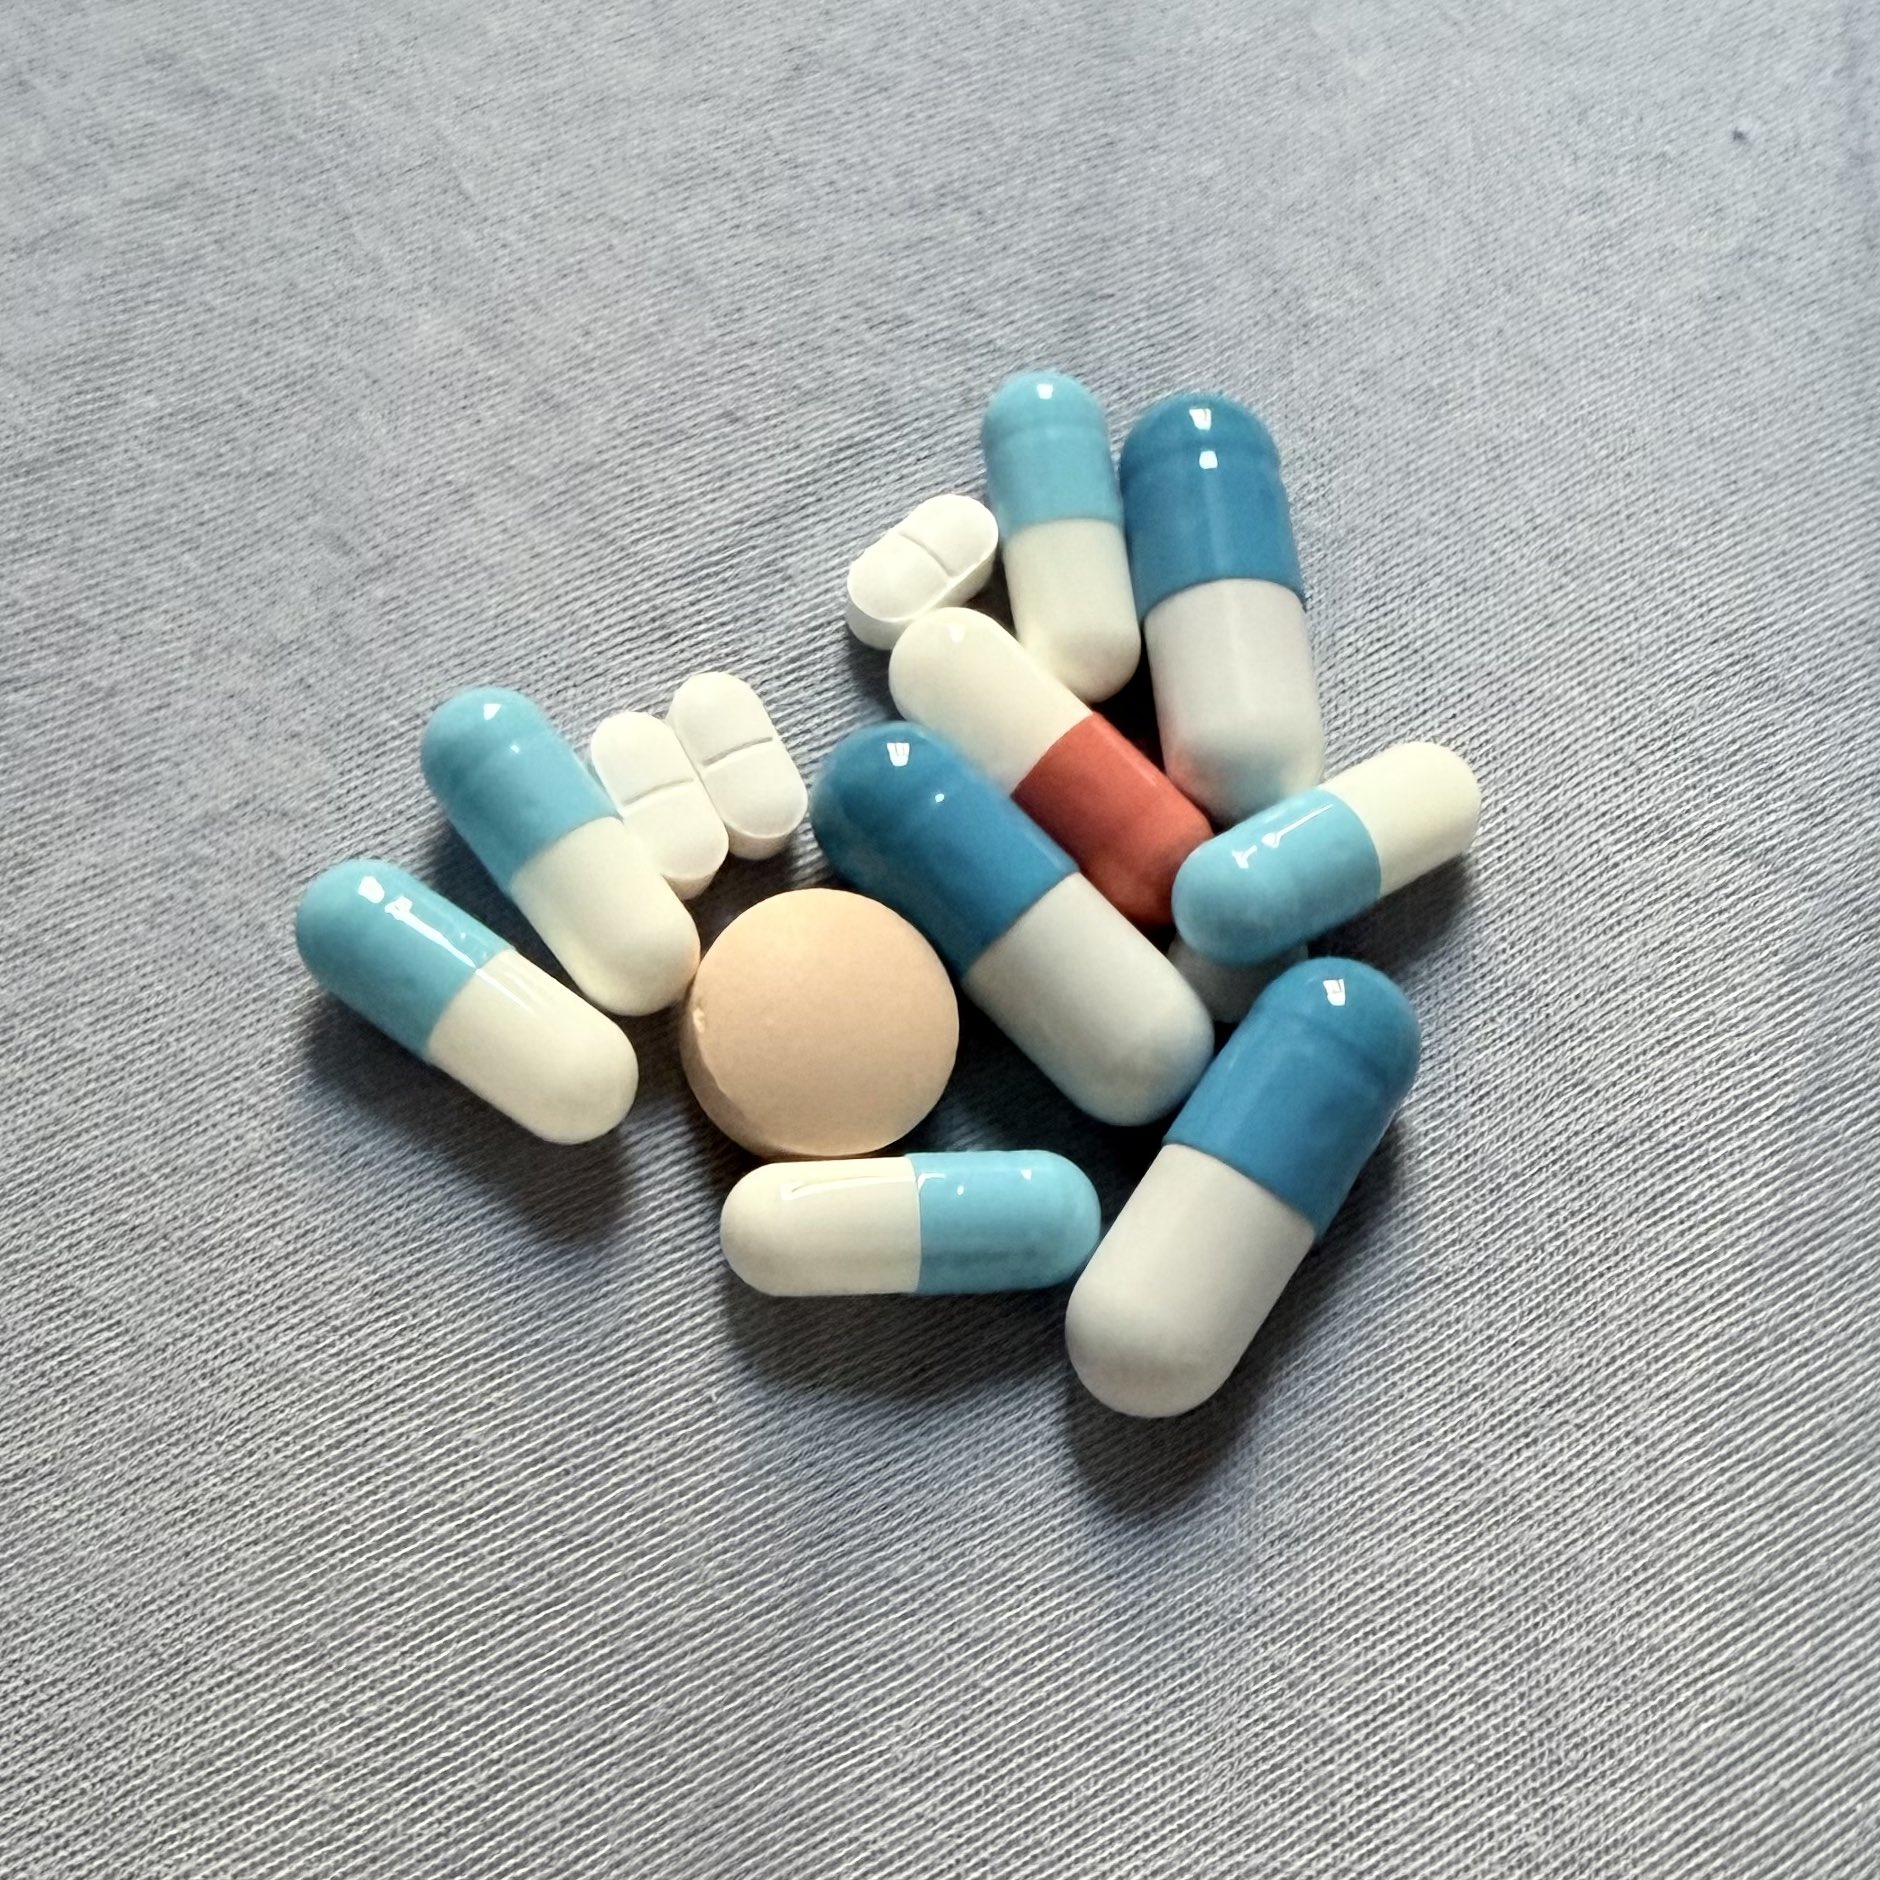

对于药物过量引起的中枢神经系统副作用,有一些不常见或常见的药物来控制症状。

罗通定:拮抗多巴胺

赛庚啶:血清素综合症

异丙嗪:在低剂量下没有抗精神病作用,和其他所有抗组胺药一样可以缓解过敏。止吐

喹硫平:不清楚是什么引起的症状就干脆谁都别玩了吧()似乎很万能的急救

评论区欢迎补充 https://t.co/7S4tGVDEM5